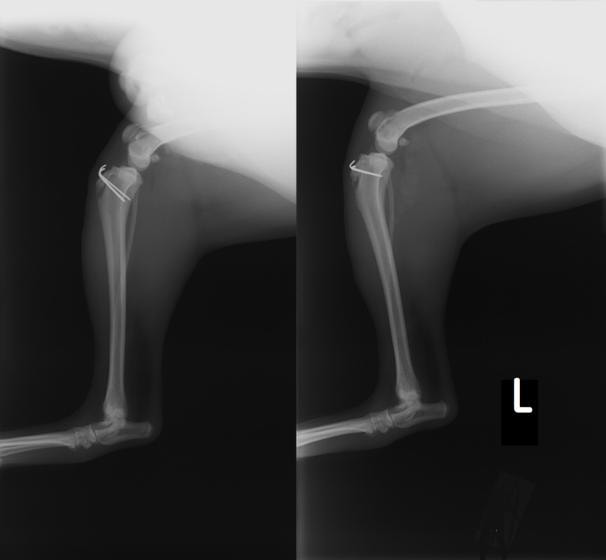

■ 症例22 ポメラニアン 1歳5か月 去勢雄

左後肢の挙上を主訴に来院した。整形学的検査、レントゲン検査より左右の膝蓋骨脱臼(左GradeⅡ〜Ⅲ、右Grade Ⅱ)を認めた。また、脛骨の前方引き出し試験の際に、引き出し兆候は認められないものの、疼痛が認められたため、前十字靭帯の損傷が疑われた。術中における、目視および関節内の操作によって、前十字靭帯の損傷や過伸展といった異常が認められなかったため、膝蓋骨脱臼の整復のみ実施した。手術手技は縫工筋及び内側広筋の解放、脛骨粗面の外側転位、滑車ブロック形造溝術、内外側関節包の縫縮を実施した。本症例は跛行もなく経過良好である。しかし、頸骨高平部の角度(TPA)が 右26.2°、左24.9°であり、解剖学的に前十字靭帯損傷のリスクが高いことから今後の経過に注意が必要である。